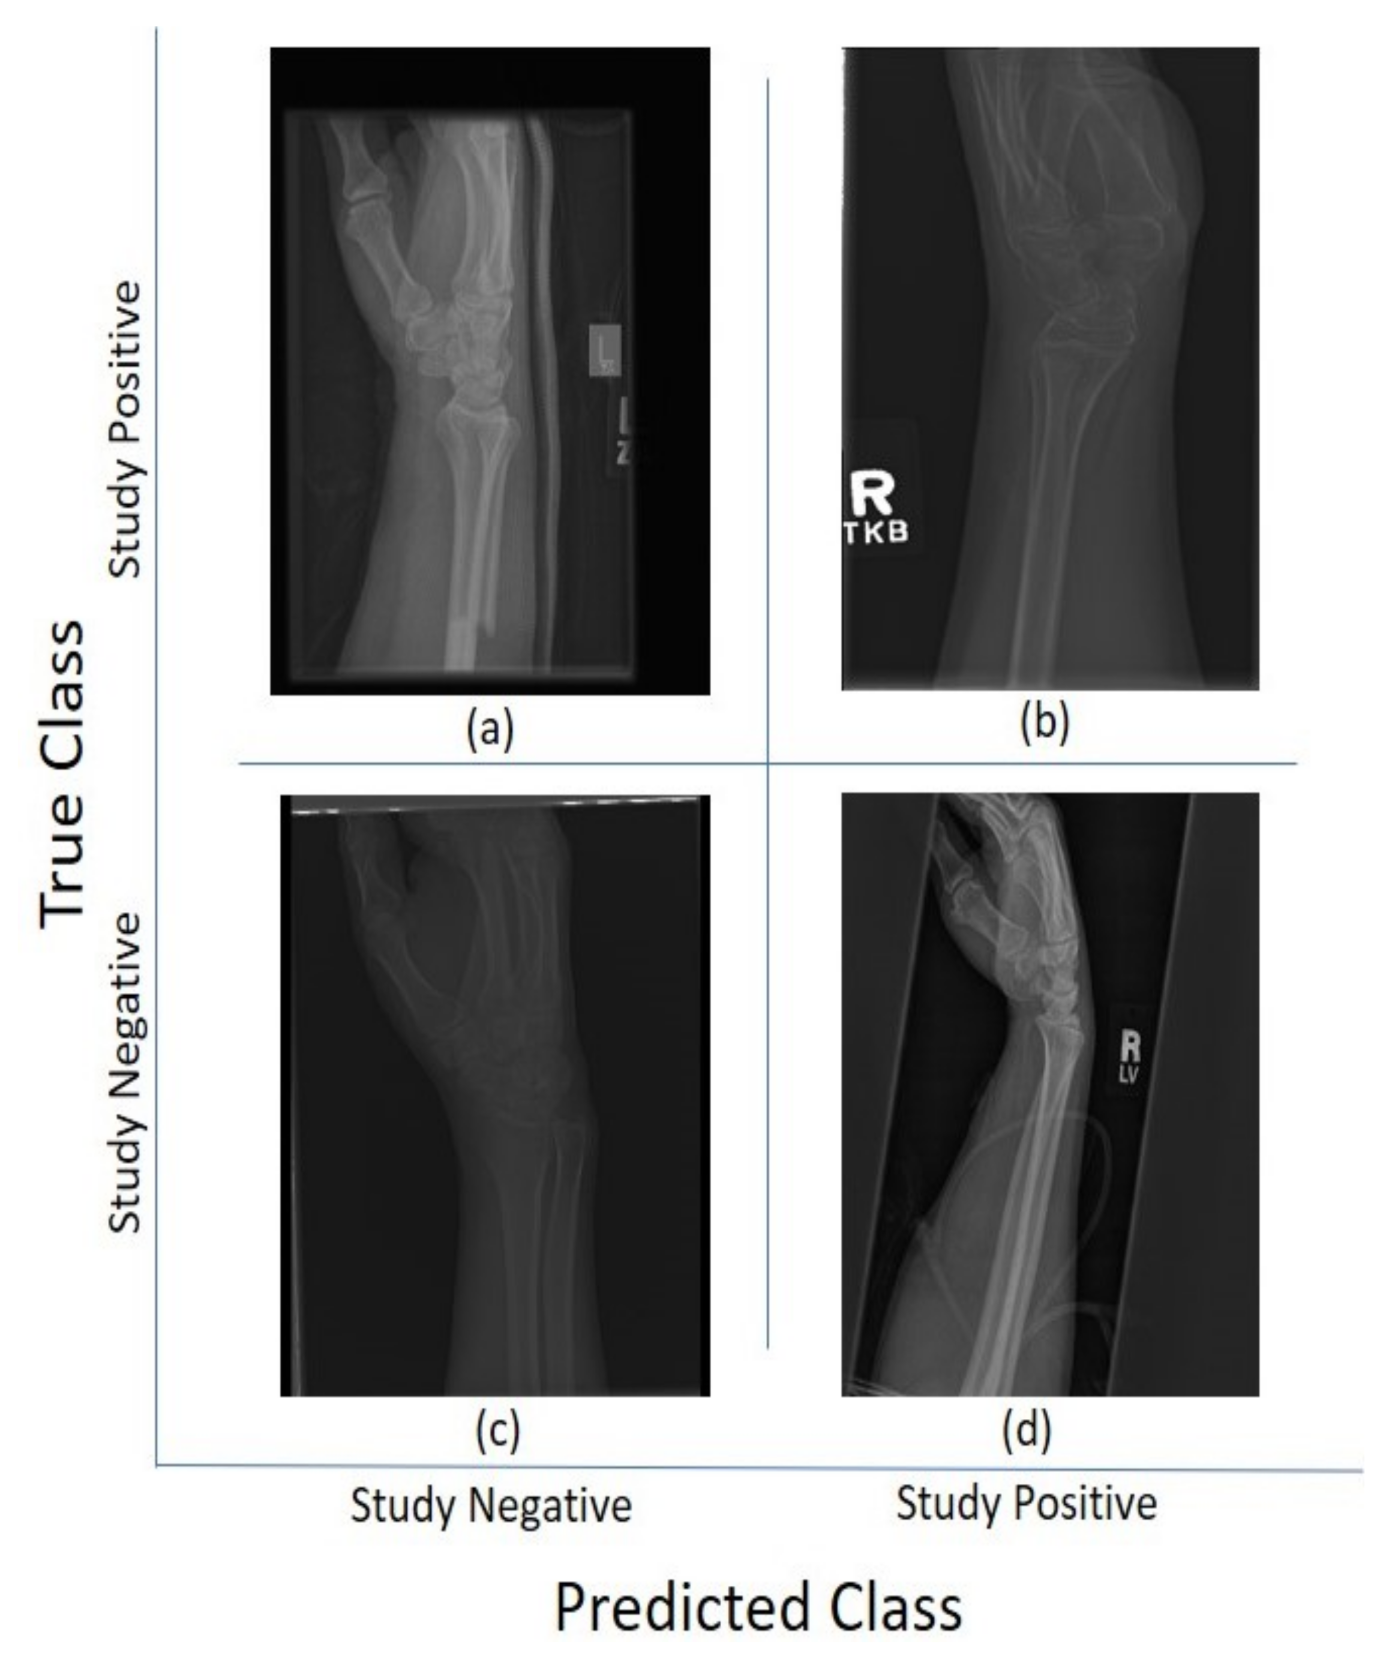

For the 11 architectures with no data augmentation, Inception-Resnet-v2 performs the best with an accuracy () and Cohen’s kappa (). DenseNet-201 fares slightly lower (, ). The lowest results were obtained with GoogleNet (, ). This potentially indicates better feature extraction with deeper network architectures. Figure 5 and Figure 6 illustrate some cases of the classification for Lateral and Postero-anterior views of wrist radiographs.

Figure 5.

Illustration of classification results for lateral (LA) views of wrist radiographs. (a) Corresponds to positive (abnormal) diagnosis image but predicted as negative (normal), (b) Abnormal diagnosis and abnormal prediction. (c) Normal diagnosis image and normal prediction. (d) Normal diagnosis and abnormal prediction. Notice that the errors in classification may have been biased by artefact elements on the images.

Figure 6.

Illustration of classification results for postero-anterior (PA) views of wrist radiographs. (a) corresponds to a positive (abnormal) diagnosis image that is predicted as negative (normal); (b) to abnormal diagnosis and abnormal prediction; (c) to normal diagnosis image and normal prediction; and (d) to normal diagnosis and abnormal prediction. Notice again that the errors in classification may have been biased by artefactual elements on the images.